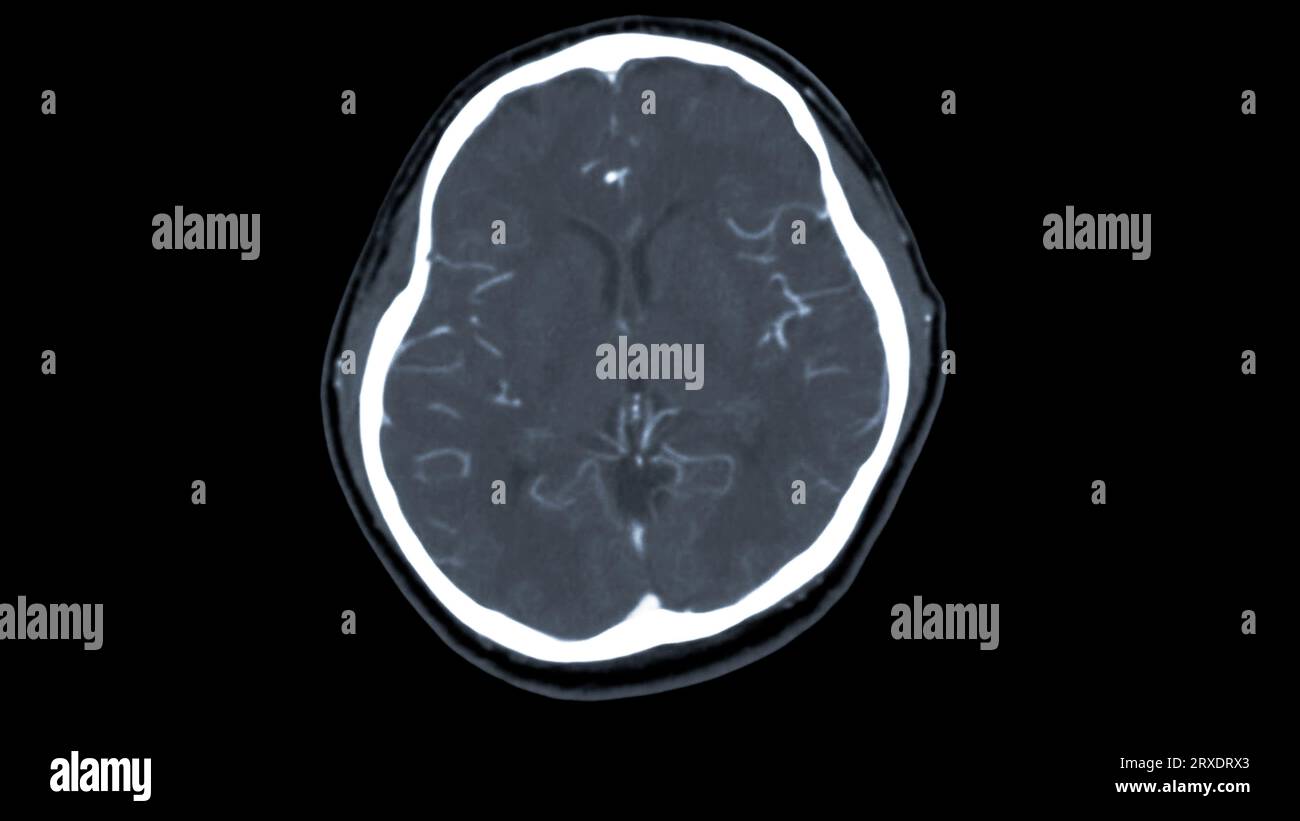

Scanner du cerveau avec le produit de contraste d'injection pour le diagnostic de tumeur cérébrale, les maladies d'AVC et les maladies vasculaires. Banque D'Imageshttps://www.alamyimages.fr/image-license-details/?v=1https://www.alamyimages.fr/scanner-du-cerveau-avec-le-produit-de-contraste-d-injection-pour-le-diagnostic-de-tumeur-cerebrale-les-maladies-d-avc-et-les-maladies-vasculaires-image567016971.html

Scanner du cerveau avec le produit de contraste d'injection pour le diagnostic de tumeur cérébrale, les maladies d'AVC et les maladies vasculaires. Banque D'Imageshttps://www.alamyimages.fr/image-license-details/?v=1https://www.alamyimages.fr/scanner-du-cerveau-avec-le-produit-de-contraste-d-injection-pour-le-diagnostic-de-tumeur-cerebrale-les-maladies-d-avc-et-les-maladies-vasculaires-image567016971.htmlRF2RXDRX3–Scanner du cerveau avec le produit de contraste d'injection pour le diagnostic de tumeur cérébrale, les maladies d'AVC et les maladies vasculaires.

Scanner du cerveau avec le produit de contraste d'injection pour le diagnostic de tumeur cérébrale, les maladies d'AVC et les maladies vasculaires. Banque D'Imageshttps://www.alamyimages.fr/image-license-details/?v=1https://www.alamyimages.fr/scanner-du-cerveau-avec-le-produit-de-contraste-d-injection-pour-le-diagnostic-de-tumeur-cerebrale-les-maladies-d-avc-et-les-maladies-vasculaires-image567016972.html

Scanner du cerveau avec le produit de contraste d'injection pour le diagnostic de tumeur cérébrale, les maladies d'AVC et les maladies vasculaires. Banque D'Imageshttps://www.alamyimages.fr/image-license-details/?v=1https://www.alamyimages.fr/scanner-du-cerveau-avec-le-produit-de-contraste-d-injection-pour-le-diagnostic-de-tumeur-cerebrale-les-maladies-d-avc-et-les-maladies-vasculaires-image567016972.htmlRF2RXDRX4–Scanner du cerveau avec le produit de contraste d'injection pour le diagnostic de tumeur cérébrale, les maladies d'AVC et les maladies vasculaires.

Scanner du cerveau avec le produit de contraste d'injection pour le diagnostic de tumeur cérébrale, les maladies d'AVC et les maladies vasculaires. Banque D'Imageshttps://www.alamyimages.fr/image-license-details/?v=1https://www.alamyimages.fr/scanner-du-cerveau-avec-le-produit-de-contraste-d-injection-pour-le-diagnostic-de-tumeur-cerebrale-les-maladies-d-avc-et-les-maladies-vasculaires-image567016966.html

Scanner du cerveau avec le produit de contraste d'injection pour le diagnostic de tumeur cérébrale, les maladies d'AVC et les maladies vasculaires. Banque D'Imageshttps://www.alamyimages.fr/image-license-details/?v=1https://www.alamyimages.fr/scanner-du-cerveau-avec-le-produit-de-contraste-d-injection-pour-le-diagnostic-de-tumeur-cerebrale-les-maladies-d-avc-et-les-maladies-vasculaires-image567016966.htmlRF2RXDRWX–Scanner du cerveau avec le produit de contraste d'injection pour le diagnostic de tumeur cérébrale, les maladies d'AVC et les maladies vasculaires.